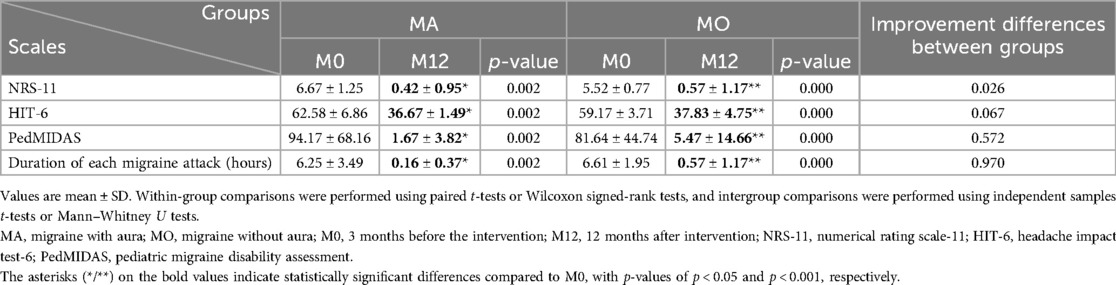

Most patients exhibited varying degrees of improvement in migraine symptoms after PFO closure. At the 1-month follow-up after the intervention, 20 patients (57.1%) achieved complete remission, and 29 (82.9%) experienced a reduction in migraine frequency of >50%. At the 12-month follow-up, 28 patients (80%) achieved complete remission, and 32 (91.4%) experienced a reduction in migraine frequency of >50%. There were no cases of worsening migraine after PFO occlusion. The NRS-11, HIT-6, PedMIDAS, migraine frequency, and migraine duration of all the children three months before the intervention, at 1 month after the intervention, and at 12 months after the intervention are shown in Table 2, which demonstrates a significant decrease in the main clinical outcome indicators of migraines from baseline to 12 months after the intervention. Notably, there were statistically significant differences between pre-intervention and one-month post-intervention data, as well as between pre-intervention and 12-month post-intervention data (p < 0.05). One year after PFO closure, only one patient continued to use the prophylactic migraine medication flunarizine, whereas two patients used analgesics solely during migraine attacks.

The reduction in NRS-11 at 12 months after intervention was more pronounced in the aura group than in the non-aura group (P < 0.05), while there were no statistically significant differences between the two groups in terms of HIT-6, PedMIDAS, and migraine duration (Figure 6, Table 4).

Figure 6. Changes in headache-related scores in children with migraine with aura and in those with migraine without aura after patent foramen ovale closure.

Table 4. Headache-related scores at different time points after patent foramen ovale closure in children with migraine with aura and in those with migraine without aura.

Our study demonstrated significant therapeutic benefits of PFO closure in pediatric migraine patients with moderate-to-large right-to-left shunts. At the 1-month follow-up after intervention, 20 patients (57.1%) achieved complete remission, and 29 (82.9%) experienced a reduction in migraine frequency of >50%. At the 12-month follow-up, 28 patients (80%) achieved complete remission, and 32 (91.4%) experienced a reduction in migraine frequency of >50%. During the 12-month follow-up period, the headache-related scores decreased significantly compared to pre-intervention levels, with statistical significance. Both the aura and non-aura groups demonstrated high response rates (83% vs. 78.3% complete remission; 100% vs. 87% achieving >50% frequency reduction), with no statistically significant intergroup differences (Figure 5, Table 3). The reduction in NRS-11 at 12 months after intervention was more pronounced in the aura group than in the non-aura group (P < 0.05), while there were no statistically significant differences between the two groups in terms of HIT-6, PedMIDAS, and migraine duration. Moreover, no serious adverse events occurred, supporting the safety of the procedure. These findings support the potential therapeutic value of PFO closure in selected pediatric migraine patients, particularly in those demonstrating medication-refractory symptoms coupled with objectively confirmed moderate-to-large right-to-left shunts.